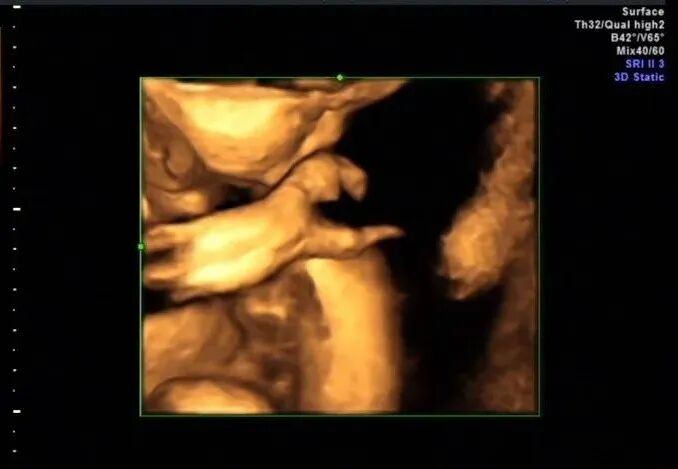

再看脚也不对劲,马上启动三维超声,下图是三维超声表现

手脚都有问题,呈龙虾爪样,非常典型的手裂足裂,胎儿父母没有啥疾病

裂手(足)畸形又称分裂手( 足)、裂掌( 足)、龙虾爪手( 足) 畸形, 是一种罕见的染色体显性遗传病, 可能由染色体长臂7q21q22缺陷所致。另一种裂手、裂足综合征和缺指/ 趾畸形、外胚层发育不良及面裂综合征( EEC) 的患者则有染色体3q27上的p63基因突变。

裂手、裂足畸形也可见于羊膜带粘连序列征。裂手、裂足可单为裂手或裂足畸形,也可两者同时发生,不论是裂手或裂足一般均发生在双侧。手纵裂分为桡、尺侧两部分,故称“龙虾手”,重者可缺4指, 仅拇指或小指残余。裂足表现似裂手, 重者近侧分裂至跗骨, 常伴跗骨异常, 跖骨缺如或趾畸形, 形成“龙虾足”,趾畸形而拇趾和小趾常存在。其主要二维声像特征为在纵切手掌时可见2个增大的手指, 且彼此间的距离明显分开至掌水平中部, 两手掌的第3掌骨缺失,根据这些特征即可明确诊断。临床上将裂手分两种类型, 中心型: 由近中心轴线的缺陷所致, 第3 列骨发育抑制最严重, 手掌中央有一深纵裂, 将手掌分成两部分, 常有一个或多个指列缺损, 残余指常倾向融合或长短不一;中间偏桡侧型: 主要累及第2列或第1列的骨骼结构, 纵裂V型顶点指向第1掌骨, 掌有一个横行骨位于第2 和第3 掌骨远端, 与邻近指的掌指关节接触, 可能是从正常解剖位置上挤出来的近节指骨, 但横行骨上没有肌腱和肌肉附着。